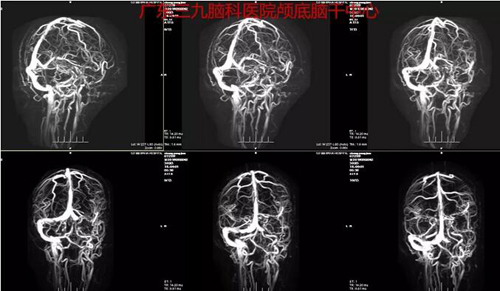

图1:术前CTA结果示左侧后颅窝占位性病变,其内示多发细小血管影,周缘较多血管包绕,邻近左侧大脑后动脉稍受压向右侧移位;双侧颈内动脉虹吸部管壁示多发钙化斑